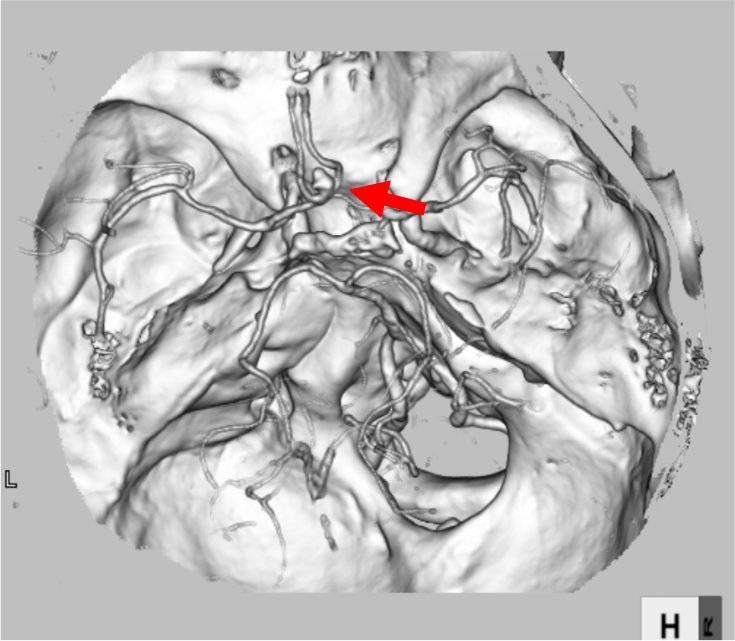

勤務中に急に意識消失し救急要請された。収縮期血圧200㎜Hgを超える高血圧も伴い、脳卒中が疑われた。頭部CTではクモ膜下腔に広範に広がる血腫を認め、くも膜下出血と診断された。前交通動脈にブレブを伴う歪な動脈瘤を認め、責任病変が疑われた。

当該疾患の診断における造影CTの役割

意識障害の原因の一つとして脳卒中があり、その中の一つにくも膜下出血が含まれる。くも膜下出血の診断は単純CTで行われる。くも膜下出血の原因の多くが脳動脈瘤の破裂である。脳動脈瘤の検索にCT angiographyが有用であり、侵襲性が少なくアクセスのしやすさからも好まれる。Volume Rendering (VR) 像は全体を俯瞰でき動脈瘤を容易に認識できることが多いが、サイズや形態により動脈瘤が分かりにくいこともあるため、元画像の確認を怠らないことが大切である。また、脈瘤破裂の他、脳動静脈奇形や脳動脈解離もくも膜下出血の原因となり、これらの有無も合わせて確認する必要がある。